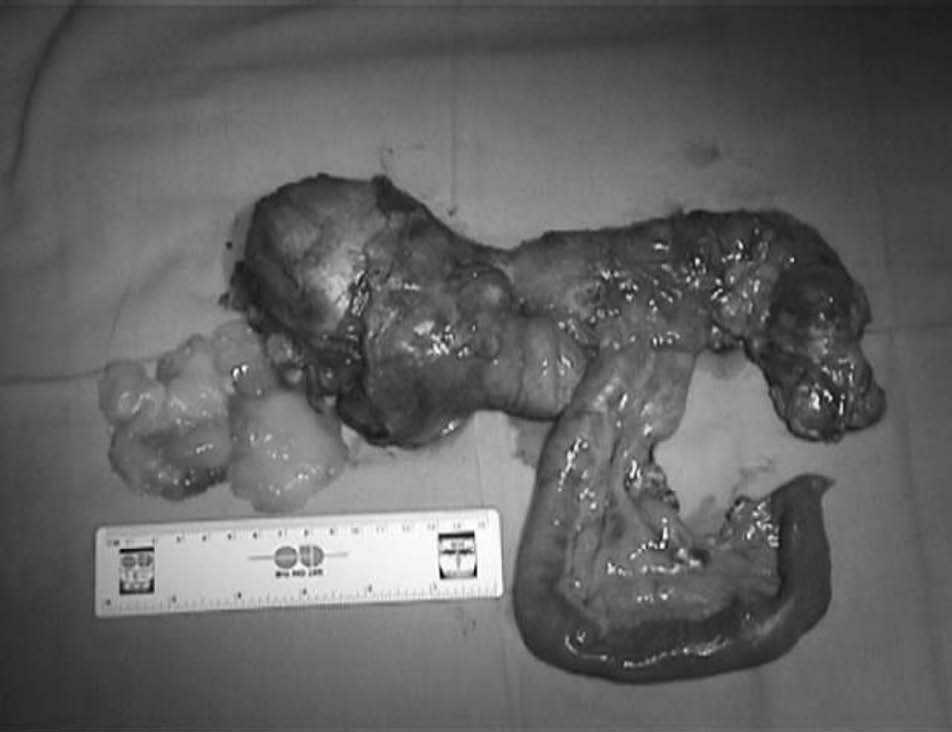

Varón de 76 años que presenta una masa blanda, no pulsátil e indolora en el hemiabdomen derecho. La tomografía computarizada (TC) helicoidal muestra una tumoración quística infracecal de 20 cm (fig. 1). En la punción-aspiración con aguja fina (PAAF) se obtiene material mucoide sin signos citológicos de malignidad. Se practicó una hemicolectomía derecha por una gran tumoración quística dependiente del ciego (fig. 2) cuyo informe anatomopatológico correspondió a un cistoadenoma apendicular.